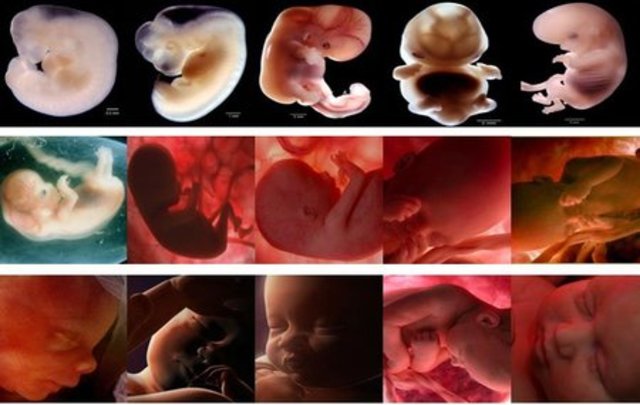

• Semana 1

Semana 1

Durante la primera semana ocurre la fecundación, la

unión de la célula femenina con la masculina. Cada una

tiene 23 cromosomas, juntas crean una célula de 46

cromosomas que viajara del tercio medio de la trompra

de Falopio hasta el útero, en donde se implantará para

iniciar su desarrollo.

• Semana 2

Semana 2

Empieza a desarrollar los cimientos de lo que serán sus órganos, sus rasgos y su sistema nervioso.Aparecen dos pequeñas cavidades oculares y la formación de sus o rejitas y sus ojos entran en una fase primaria.

También se empieza a desarrollar el tubo neural, un tubo al descubierto sin piel ni huesos que se convertirá en el cerebro, la médula espinal y el sistema nervioso y la columna

vertebral. volumen de sangre aumenta en un 50%.

• Semana 3

Semana 3

Se forma el tubo neuronal y comienza a apreciarse una extremidad abultada: la cabeza. Se desarrollan las primeras células nerviosas

Nacen células que dan impulsos eléctricos lo que hace que tenga sus primeros latidos y el cerebro.

• Semana 4

Semana 4

Principia el desarrollo de los ojos, de los oídos, de la boca y de la nariz. Se observan los brotes que van a dar origen a los brazos y a las piernas. La prominencia cardíaca es muy visible. Se desarrollan las vesículas cerebrales

• Semana 5

Semana 5

El embrión se ha dividido en tres capas, que darán lugar a los futuros órganos del bebé: el ectodermo, que dará lugar al sistema nervioso central; el endodermo, que dará lugar al

tracto intestinal, páncreas, hígados y glándula tiroides, y el

mesodermo, de donde surgirán los huesos, músculos y sistema

sanguíneo. El embrión asimismo esbozará enseguida la cabeza, los ojos, las orejas y los demás miembros.

• Semana 6

Semana 6

En esta semana es cuando el corazón comienza con

latidos regulares que por lo regular no se detectan

aun en la ecografía, también comienza a tener

ligeros movimientos que aún no se perciben pues su

tamaño es de aproximadamente 1 centímetro de

largo.Progresa el desarrollo de la traquea, la laringe

y bronquios. Lacavidad oral y nasal comienzan a

separarse, se forma el paladar. Se desarrollan más la

piernas y los brazos que parecen aletas.

• Semana 7

Semana 7

Se pueden observar las yemas o también llamados brotes de brazos, las extremidades inferiores en forma de pala y la placa de la mano, también pudiendo ver algunos nervios del cráneo. Esta etapa es denominada organogénesis siendo un periodo importante en la formación del bebé pues es aquí donde se pueden crear mal formaciones.

• Semana 8

Semana 8

Todos sus órganos mayores se han formado, aunque no completamente. Su cola embrionaria desaparece. El cerebro está completamente creado y las neuronas empiezan a dividirse formando el sistema nervioso.

• Semana 9

Semana 9

Se forman los pezones y los folículos pilosos.

Los brazos crecen y se desarrollan los codos.

Se pueden observar los dedos del pie del bebé.

Todos los órganos esenciales del bebé han comenzado a crecer.

• Semana 10

Semana 10

Los párpados del bebé están más desarrollados y comienzan a cerrarse.

Las orejas comienzan a tomar forma.

Las características faciales del bebé se vuelven más distintivas.

Los intestinos rotan.

Al final de la décima semana de embarazo, su bebé ya no es un embrión. Ahora es un feto, la etapa de desarrollo hasta el nacimiento.